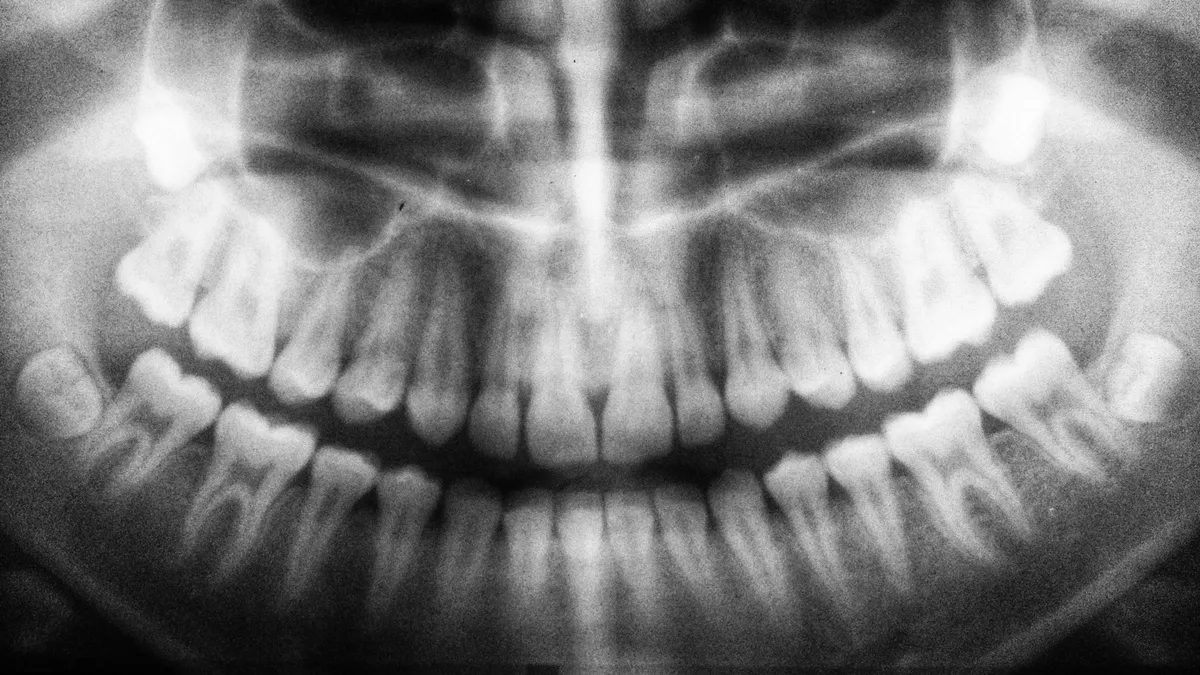

Fogorvosi látogatása során Edd egy rutin röntgenfelvételen esett át, ahol a fogorvos azt mondta, hogy nem lát csontokat. Ezt követően CT-re küldték, amely kimutatta, hogy egy daganat növekszik az arcüregének bal oldalán, ami az orra alá terjedt jobbra, és a felső állkapcsának bal oldalán nincs csont. Az orvosok közölték a férfival, hogy egy biopsziára van szükség, de mivel másnap repült haza, azt már ez Egyesült Királyságban ejtette meg szeptemberben.

Október 22-én Edd megkapta a lesújtó hírt, miszerint második stádiumú diffúz nagy B-sejtes limfómája van, ami egyfajta non-Hodgkin limfóma, és vérképzőszervi daganat. A röntgenfelvételeken látható volt, hogy daganata a felső állkapcsának bal oldalán átrágta magát.